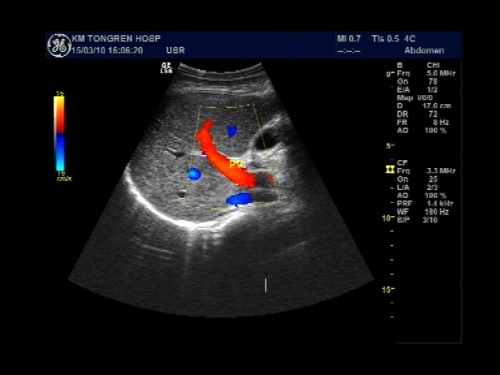

超声声像图能显示肝脏切面形态、大小、肝内实质结构、管道系统及肝周邻,并能根据肝内管道系统区分肝脏各叶、各段,对病变进行定位诊断。彩色多普勒超声能显示肝脏的血流,并能对肝脏的血流动力学参数进行测定,不仅能诊断肝脏的血管病变,还能了解正常肝脏及病变肝脏的血供及回流状态,目前已成为临床诊断肝脏疾病的常规检查方法。

彩色多普勒超声扫查

彩色多普勒能量图

肝脏血管病变:门脉海绵状变性、门静脉闭塞、肝动、静脉及门静脉栓子、门静脉-肝动脉瘘、肝动脉瘤、肝段下腔静脉阻塞综合征。